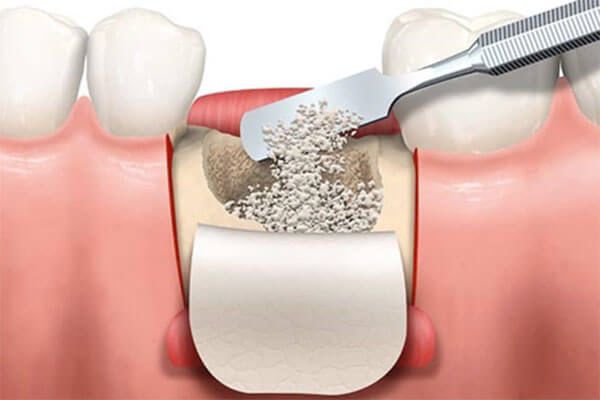

Indicado quando ocorre a perda óssea, visando acrescentar altura ou espessura do osso para permitir a colocação do implante.

Sim! Utilizamos técnicas modernas como enxerto ósseo, implante zigomático e o protocolo All-on-4, que permitem realizar o tratamento mesmo em casos com perda óssea acentuada.